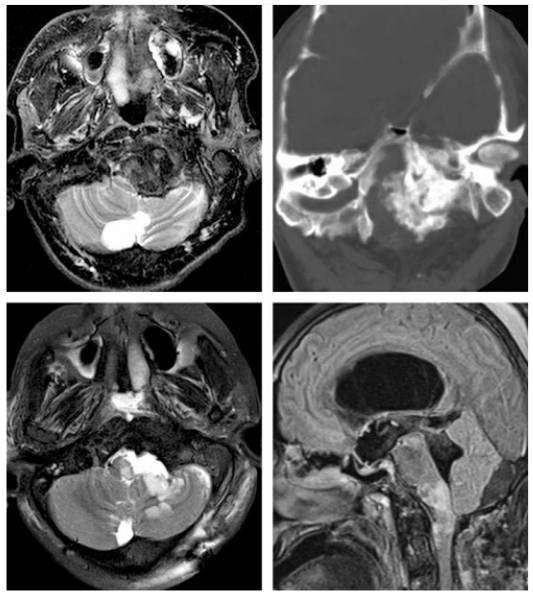

图1. 主体位于枕骨大孔腹侧的脑膜瘤采用如下所述的保守经髁切除(上图)。术后CT扫描显示(左下图)仅切除了足够显露病变的枕髁。椎动脉在穿入硬膜处用缝线牵向外侧。术中图片(右下图)显示至颅颈交界区前方硬膜充分显露和肿瘤切除后的结果。轴外病变通过内减压能够获得足够大的手术空间。

图2. 一个脑膜瘤钙化的年轻患者,观察数年直到症状严重影响其日常生活(上图)。患者在外院首次尝试切除肿瘤以失败告终。来笔者院尝试再次手术。肿瘤高度钙化使减压十分棘手,最终采用磨钻磨除肿瘤核心部分。在从脑干表面移除肿瘤包膜时,笔者不小心损伤了被包裹的椎动脉。这一激进做法导致了术后脑干梗死,最终患者不幸死亡(下图)。这一病例告诫笔者枕骨大孔区高度钙化的肿瘤减压比积极切除更重要。